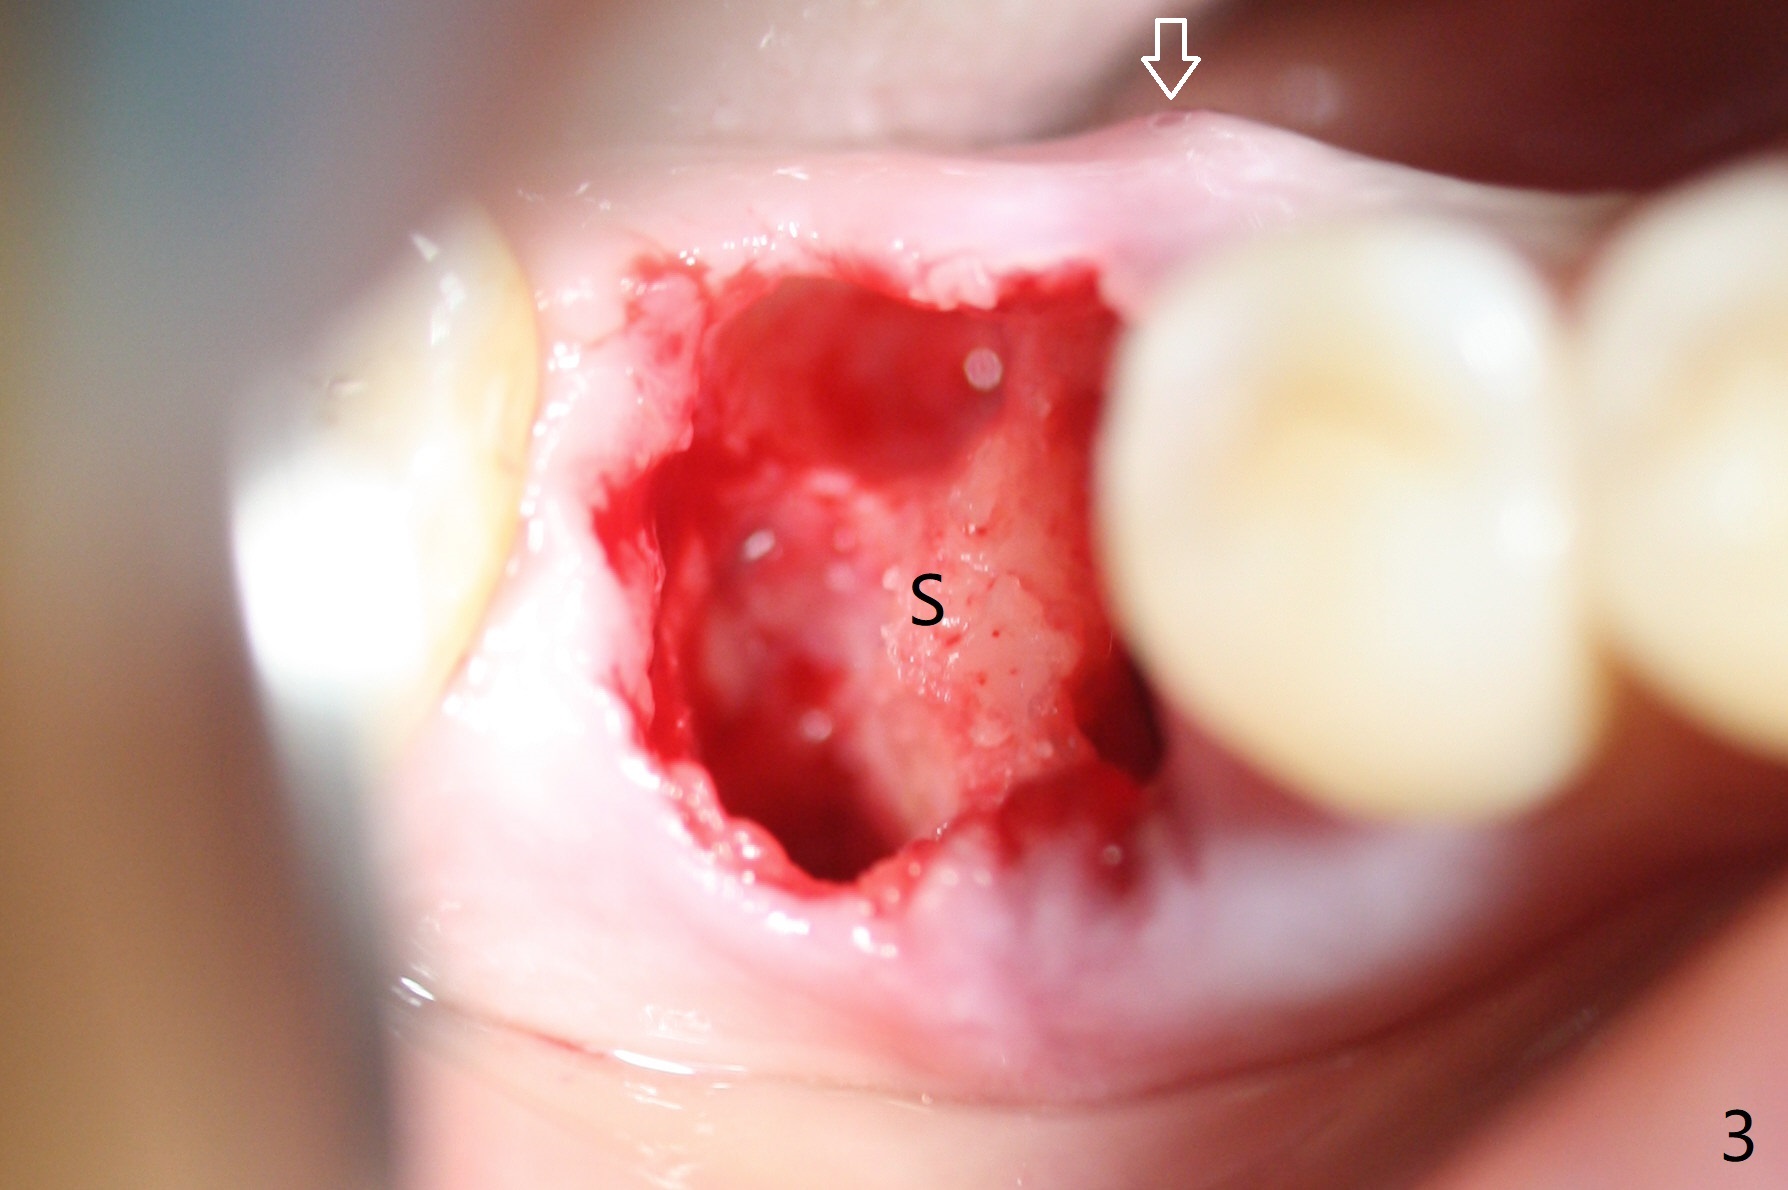

Preop oral Amoxicillin seems to be associated with reduction in the buccal and lingual (Fig.3 arrow) fistulae at #30, but there is mesiobuccal swelling (Fig.1 *) with 7 mm pocket (Fig.2). Osteotomy is initiated in the middle of the septum (Fig.3-5 S). As the osteotomy increases, it shifts mesially (Fig.6 arrow). Guided surgery is able to reduce shifting. A 5x13 mm implant is not seated completely (Fig.7) apparently due to osteotomy shifting. After removal of the bone from the osteotomy distally, the implant remains unseated with lower torque value (Fig.8). Following reuse of the 4.3 mm drill deeper by 1-2 mm, the implant is seated to a satisfactory depth (Fig.9 with increase in torque to 50 Ncm) with placement of Vera Graft (*) and a 7.5x4(3) mm abutment. After a second round of allograft placement (Fig.10 *), the implant is found to be 4 mm from the IAC. At the later stage of osteotomy, the coronal end of the septum is destroyed with loss of osteotomy depth landmark. It is apparent that the soft tissue landmark may be more reliable. The implant threads appear to be covered by the bone graft 3.5 months postop (Fig.11). The abutment is changed to 6.5x5(3) mm one before impression with minor margin prep. The bone density seems to increase 5 months postop, i.e., immediately post cementation (Fig.12) and 10 months postop (5 months post cementation (after retightening abutment), Fig.13 (*)). Periimplantitis develops mesiobuccally, consistent with bone loss 1 year 7 months post cementation (Fig.14 *); the implant seems to have been buccally placed. Bone graft is necessary with PRF or GEM21S if the vein is small and 6-month membrane with a hole around a 7.5x4(4) cemented abutment for easy wound closure. Take 5x5 CM CBCT to determine which wall has defect, buccal or lingual. Check mesial contact. If so, remove the crown, reseat the abutment (possible incomplete seating) and re-impress after bone graft.